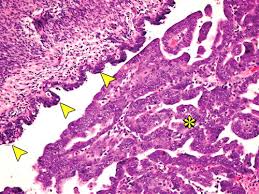

Diagnostics Free Full Text Differential Diagnosis Of Endometriosis By Ultrasound A Rising Challenge Html from www.mdpi.com It is unclear what causes ovarian cancer, but risk factors include a family history of the condition and mutations in certain genes. While there are similarities between endometriosis and ovarian cancer, difference are apparent as well. Ovarian cancer can indeed be mistaken for endometriosis. Answer from tatnai burnett, m.d. I am 42 years old, and have been experiencing perimenopausal symptoms for about 4 years. Ovarian cysts are often identified when an ultrasound examination is performed for another reason. These are the eight conditions that endometriosis is often mistaken for. Many other symptoms can have similar symptoms such as endometriosis, fibroids uterine myomas, gastrointestinal conditions such as colitis, ibs, diverticulosis and benign ovarian cysts. what makes the situation more vexing is if the patient has only a few symptoms.